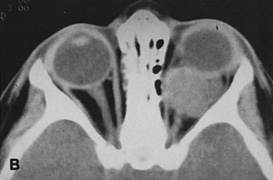

Magnetic resonance imaging is useful in selected cases, especially when evaluating the orbital cranial junction. Significant bony artifact and a lack of orbital fat in the orbital apex make CT scan resolution of the orbital apex structures poor. Because cortical bone has low signal on MRI, there is no bone artifact when viewing the orbital apex on MRI. The lack of intervening fat in the apex to provide contrast is overcome on MRI because contrast is provided by the individual nuclear characteristics of each tissue so that the orbital apex structures are visualized well. Consequently, conditions that affect the optic nerve and chiasm, such as optic nerve meningioma and glioma, generally are evaluated with MRI rather than CT scan (Fig. 2).

Fig. 2. A. Axial orbital CT scan of right optic nerve meningioma. Note lack of detail in orbital apex. B. Axial orbital MR image, same patient. Note increased detail in orbital apex owing to lack of bone artifact. C. MRI with gadolinium contrast. Note extension into brain not easily appreciated with CT scanning or MRI without contrast.